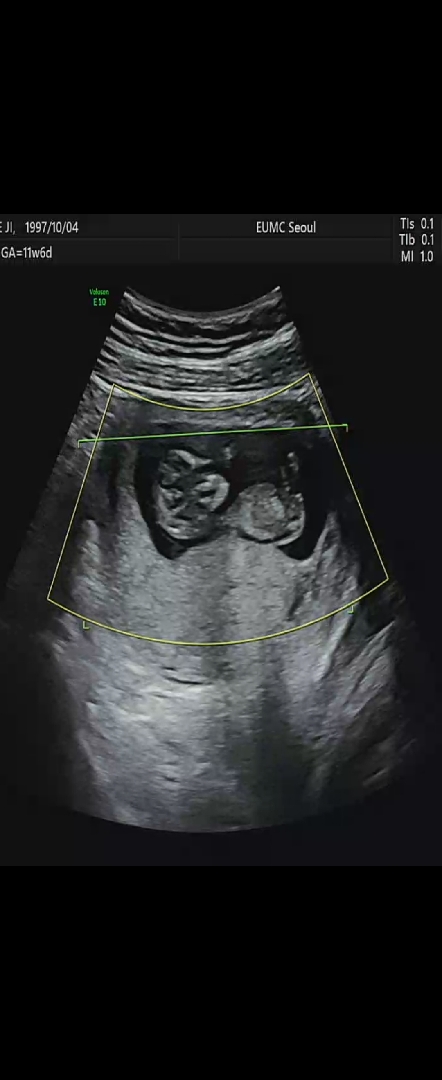

12주 각도법 봐주세요

각도법 보실수 있는분들!! 어떠세요?? 한번 봐주세요!!